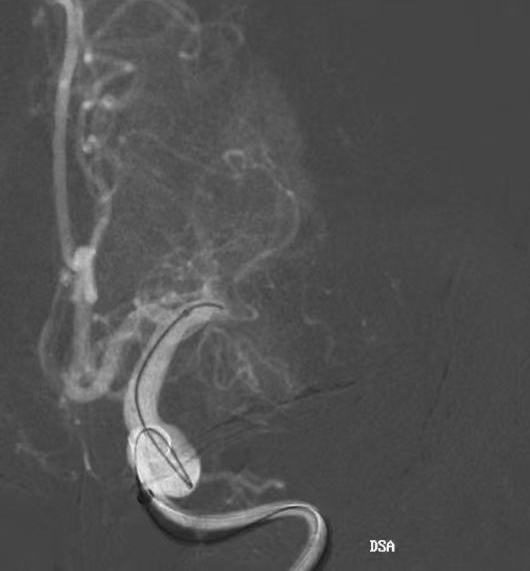

计划撤出内部器械前充盈近端BMAX088球囊长鞘,阻断前向血流,并持续抽吸提供负压。

取栓支架置于大脑中动脉水平段,中间导管在闭塞近端持续抽吸,在BMAX088球囊长鞘近端负压保护下,将支架及中间导管撤出。

确认血栓完全取出后,球囊泄压,术后即刻造影显示大脑中动脉闭塞再通, mTICI评分3级。